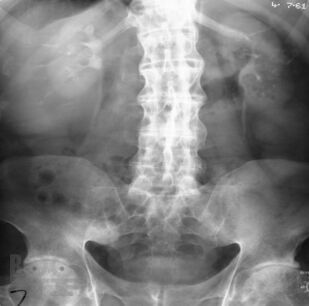

В данном учебном пособии отображены основные критерии клиники, диагностики и реабилитационного лечения суставного синдрома на амбулаторном этапе. Также представлены ведущие факторы риска развития суставного синдрома, его дифференциальная диагностика и алгоритмы ведения пациентов в условиях первичного звена здравоохранения. Отображены особенности течения инфекционного и неинфекционного поражения суставов, рассмотрены современные аспекты реабилитационного лечения данной группы пациентов. Рассмотрены вопросы профилактики и ранней диагностики поражений суставов. Учебное пособие предназначено для студентов старших курсов медицинских вузов, клинических ординаторов, участковых терапевтов и семейных врачей, врачей смежных специальностей первичного звена здравоохранения.